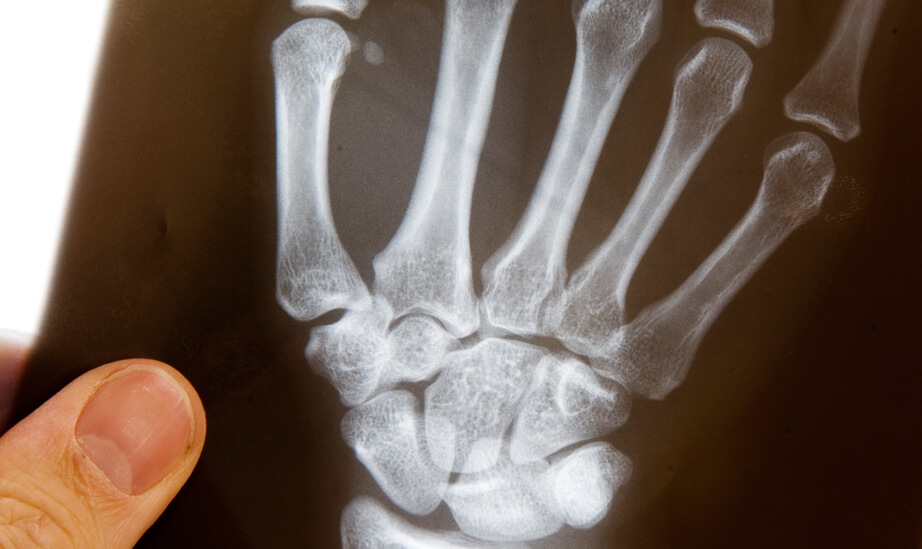

Ziel der Handrehabilitation-Therapie ist eine schnellstmögliche Wiederherstellung aller gestörten Funktionen für einen uneingeschränkten Einsatz der Hand in Alltag, Beruf und Freizeit zu erreichen. Zu den typischen Erkrankungen/Verletzungen der Hand gehören z.B.: Frakturen (Knochenbrüche), Distorsionen (Verstauchungen), Luxationen (Ausrenkungen), Nervenverletzungen, Nervenkompressionssyndrome z.B. Karpaltunnelsyndrom, Erkrankungen / Verletzungen der Sehnen, schnellender Finger (Ringbandverengung), Arthrose der Hand und Fingergelenke, Rheumatische Erkrankungen, Sportverletzungen, CRPS-Syndrom (ehemals. Morbus Sudeck), Verbrennungen, Amputationen.